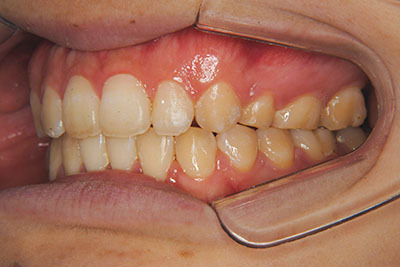

おとなの方でも矯正治療をあきらめないでください!

いくら歯が動き易くとも、本人がやる気でなければ効果は出ませんし、むし歯発生のリスクも高まります。おとなの方は顎の成長が終わっているため、治療の計画が立てやすいとも言えます。「もう大人だから…」とあきらめず、一度ご相談ください。